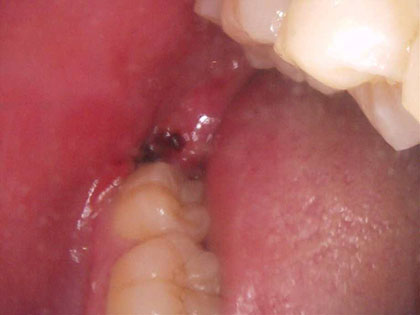

• 抜歯後の写真がこちら

• 親知らずの抜歯治療中1

• こちらを傷つけないように、歯肉を切開し、粘膜を開いて親知らず周囲の骨を削り、歯冠(頭の部分)を慎重に削り、歯根(根っこの部分)を抜歯しました。

• 最後に歯を抜いた部分を洗浄し、粘膜を開いた部分を糸で縫いました。